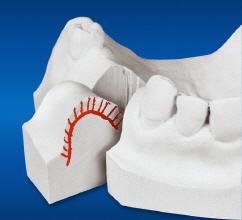

Jeder Zahnverlust verursacht Veränderungen und Abbau des zahntragenden Kieferabschnitts.

Für ein Implantat werden sowohl eine Mindest-Knochentiefe als auch ein Sicherheitsabstand im Unterkiefer zum Nervenkanal vorausgesetzt. Die Knochentiefe wird durch spezielle Röntgendiagnostik ermittelt.